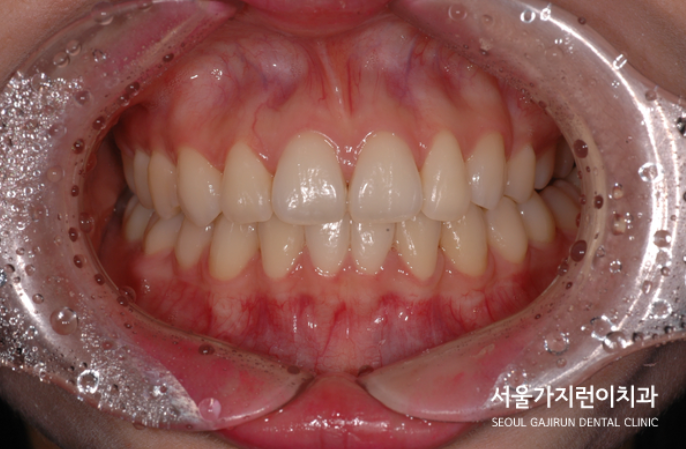

[사랑니 세우는 교정]+[덧니교정] 을 같이 진행한 사례입니다.

환자분의 경우 치열의 흐트러짐과 덧니로 인해 스트레스를 받고 계신 상황이었습니다.

이미 발치가 된 하악과 곧 발치가 필요한 어금니, 게다가 덧니와 더불어 흐트러진 치열까지 밸런스를 맞추기 쉽지 않은 케이스였는데요. 무엇보다 한쪽은 대구치, 한쪽은 소구치여서 발치 공간의 크기가 달라 중심선을 맞추고 정상 교합으로 맞추기가 쉽지 않은 경우였습니다. 하지만 저희는 교정전문치과잖아요. 사랑니를 세우는 교정과 더불어 덧니교정까지 진행해봤습니다.

발치된 공간은 임플란트를 식립하지 않고 공간을 폐쇄하는 쪽으로 진행했으며 하악의 경우에는 사랑니를 세워 새로운 어금니로 활용할 수 있도록 교정을 진행했는데요. 상하악 모두 발치 공간이 닫히는 모습을 과정 사진으로 확인할 수 있겠습니다.